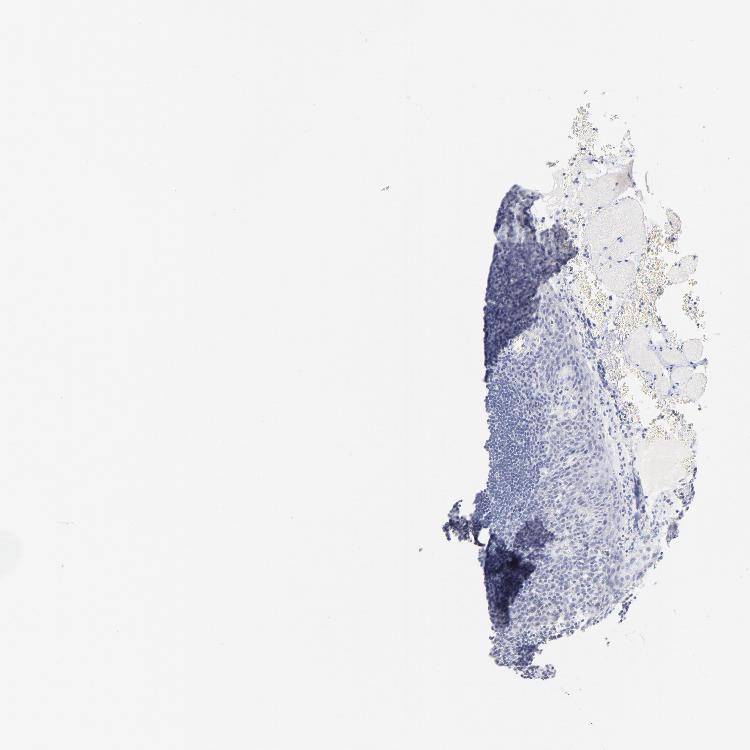

TISSUE PRIMARY DATA TONSIL Show tissue menu

Tonsil

TONSIL - Antibody stainingi

Antibody staining in the annotated cell types in the current human tissue is reported as not detected, low, medium, or high, based on conventional immunohistochemistry profiling in selected tissues. This score is based on the combination of the staining intensity and fraction of stained cells.

Each image is clickable and will lead to virtual microscopy that enables deeper exploration of all samples and also displays staining intensity scores, fraction scores and subcellular localization as well as patient and tissue information for each sample.

Antibody HPA003402

Germinal center cells Not detected

Non-germinal center cells Not detected

Squamous epithelial cells Not detected